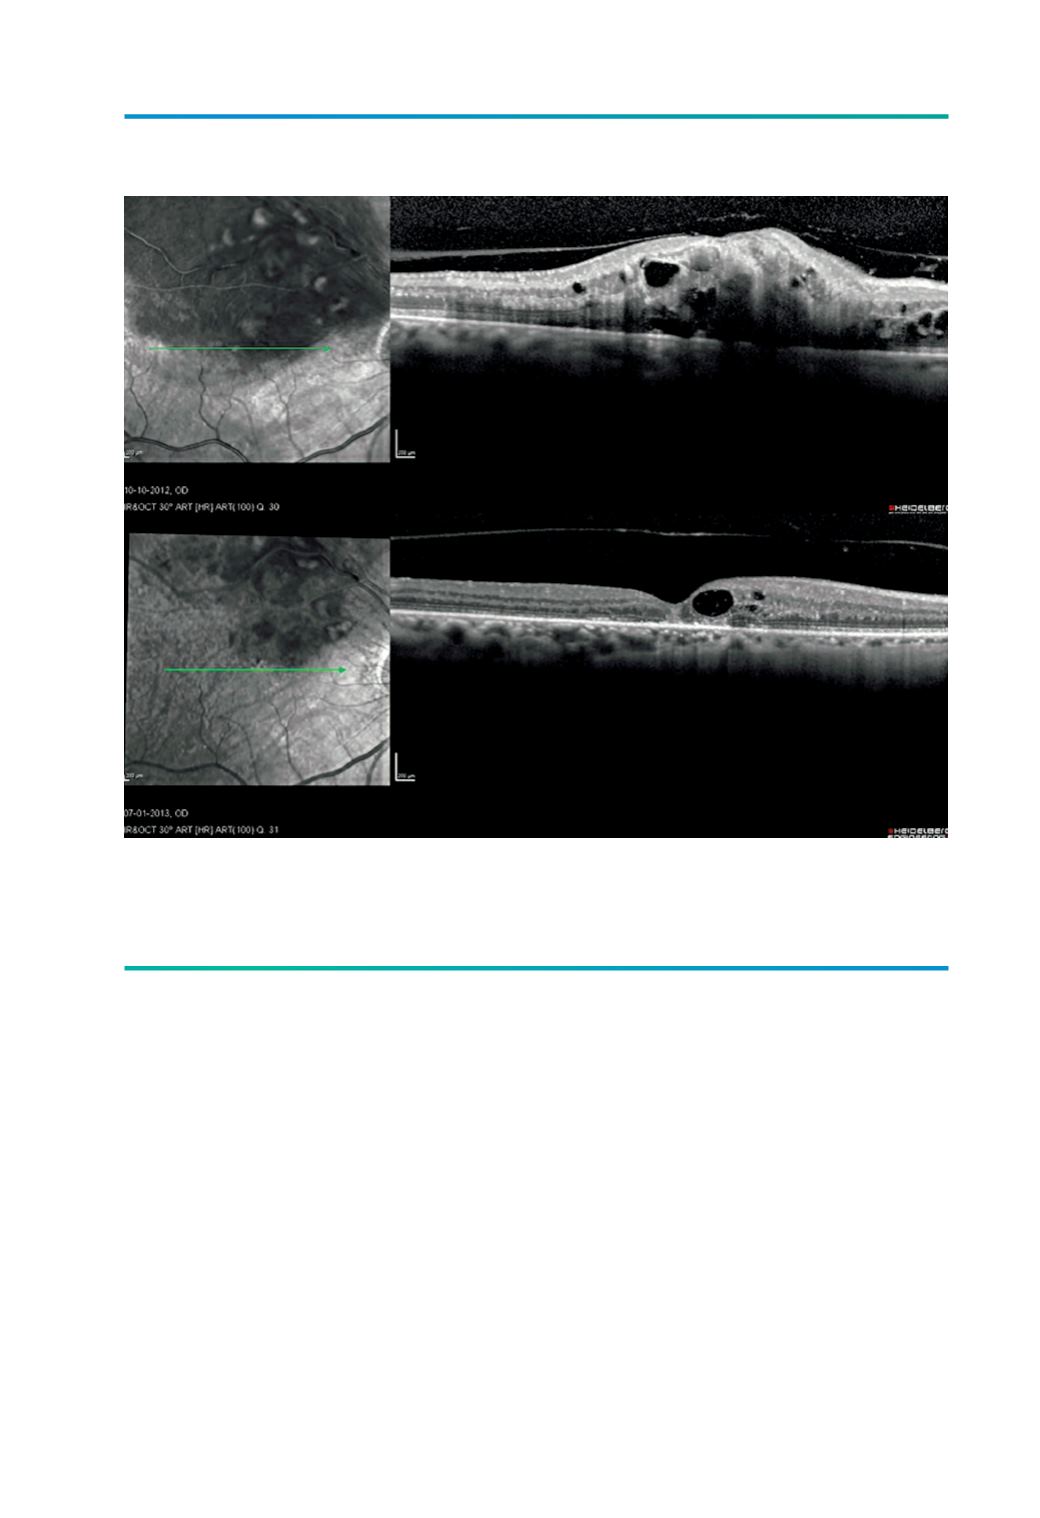

Figura 3.

OVR temporal superior, onde se observa adesão vítreo-macular na região central da mácula, que

desaparece em 3 meses. O edema macular recuperou quase completamente com duas injecções

intravítreas de bevacizumab.